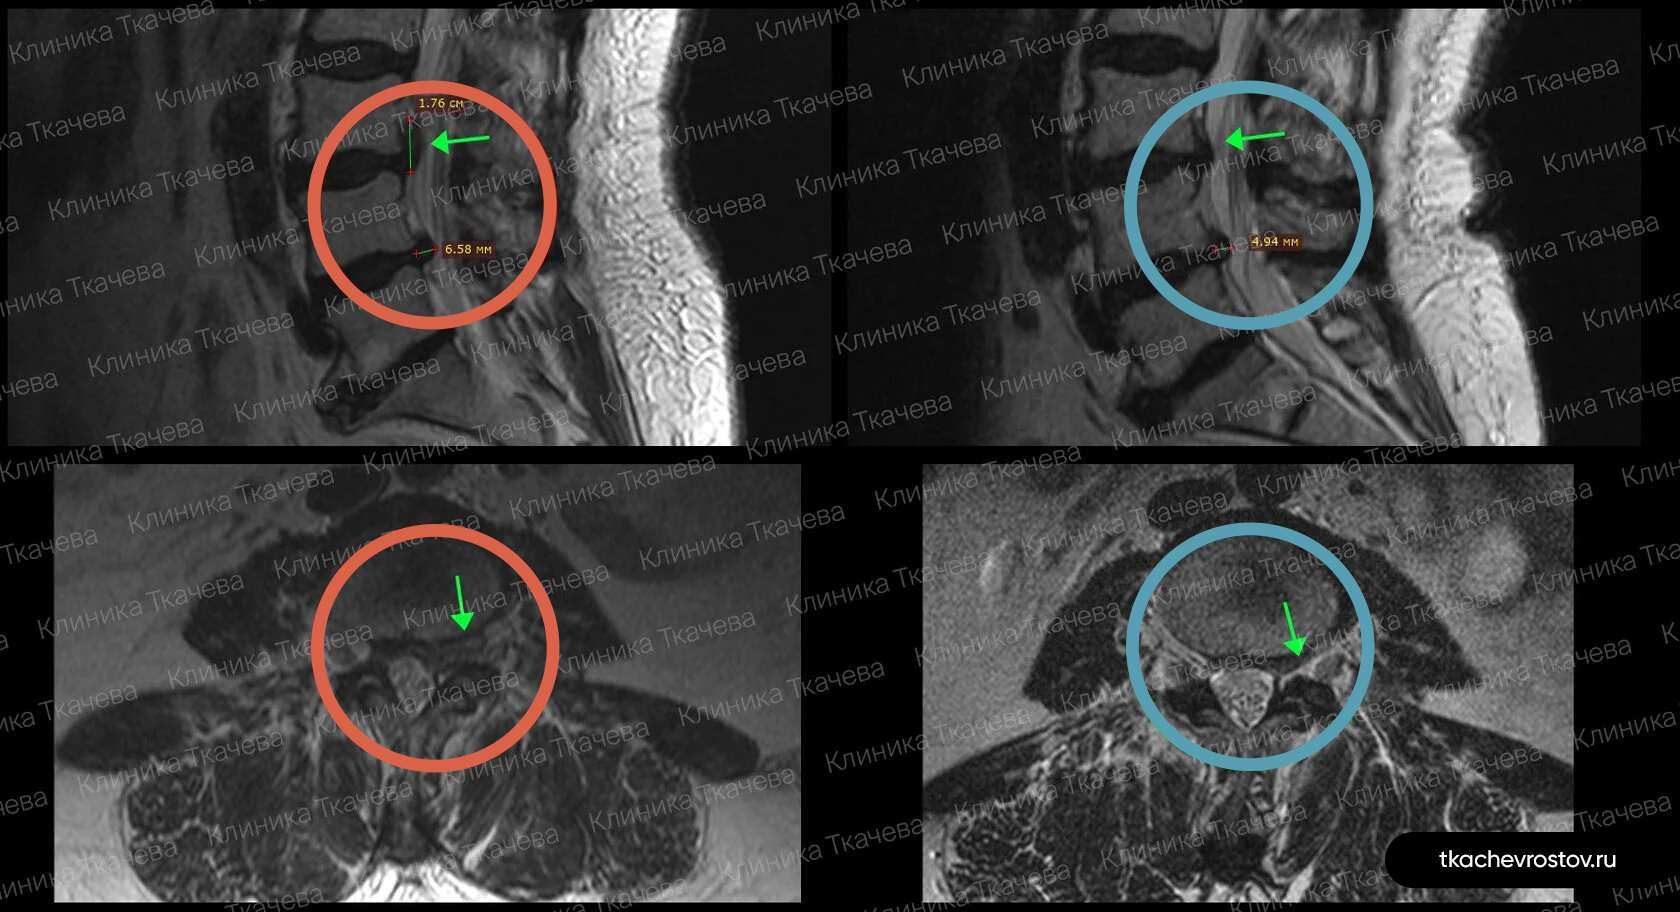

Грыжа в поясничном отделе L4-L5

Мужчина. Межпозвонковая грыжа в сегменте L4-L5 1.5 х 1.7 см с абсолютным стенозом позвоночного канала. Никакое лечение не помогло, отправили вначале к психиатру, а потом к нейрохирургу.

ДО:

- Интенсивная боль в пояснице, с эпизодическими прострелами

- Ограничение движений в пояснице

- Нарушения сна

- Снижение бытовой и социальной активности

ПОСЛЕ 1 курса:

✓ Наступила частичная резорбция грыжи

✓ Наступило улучшения общего состояния.

ПОСЛЕ 2 курса:

✓ Наступила полная резорбция грыжи

✓ Небольшое восстановление высоты межпозвонкового диска (регенерация пульпозного ядра)

Лечение грыжи заняло 8 месяцев. Было проведено 2 курса лечения по 12 дней.